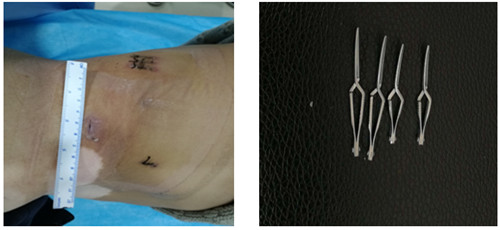

后腹腔鏡技術(shù),即俗稱的“打眼”,于腰部不同部位作3個(gè)5-12毫米的小切口,通過(guò)這些切口插入攝像鏡頭及手術(shù)器械,通過(guò)攝像鏡頭將各個(gè)組織、臟器傳輸?shù)诫娨暺聊簧希饪漆t(yī)生通過(guò)觀察圖像用各種手術(shù)器械在腰部進(jìn)行操作來(lái)完成手術(shù)。

如圖一圖二為腫瘤位置及大小,圖三即為手術(shù)操作通道(5mm、10mm、12mm),術(shù)中游離出腎動(dòng)脈后,用圖四的血管夾臨時(shí)阻斷腎臟血液供應(yīng),剜除腫瘤后,在腔鏡下縫合腎臟,確定縫合嚴(yán)密,再恢復(fù)腎臟血供!要求阻斷時(shí)間不能超過(guò)30分鐘,此例患者阻斷17分鐘!此類手術(shù)技術(shù)難度大,腹腔鏡下縫合要求高,并對(duì)血供阻斷有時(shí)間要求!